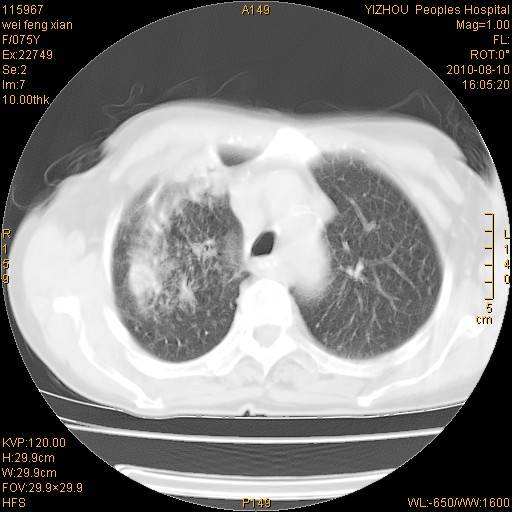

标题: CT28313:两肺弥漫性病变 [打印本页]

标题: CT28313:两肺弥漫性病变

女,75岁,患者反复头昏乏力面色苍白3年,再发10天入院。临床贫血查因。

双肺间质增生并右肺上叶炎性改变,不除外右肺上叶结核病肺内播散

考虑尘肺并结核;右上肺支气管扩张!

结核、尘肺、支气管肺泡癌都不能除外

右肺上叶继发性肺结核伴肺内血型播散!

考虑右肺上叶继发性肺结核伴两肺播散。